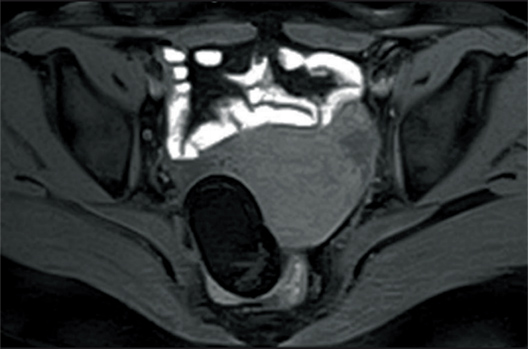

T2WI